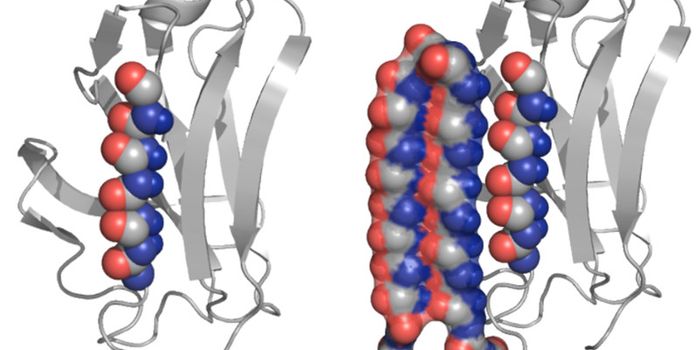

JAN 26, 2016CancerTSRI and UC Berkeley Team Solves Structure of 'Flipping' Cellular Machine, Pointing to Possible Alzheimer’ ...